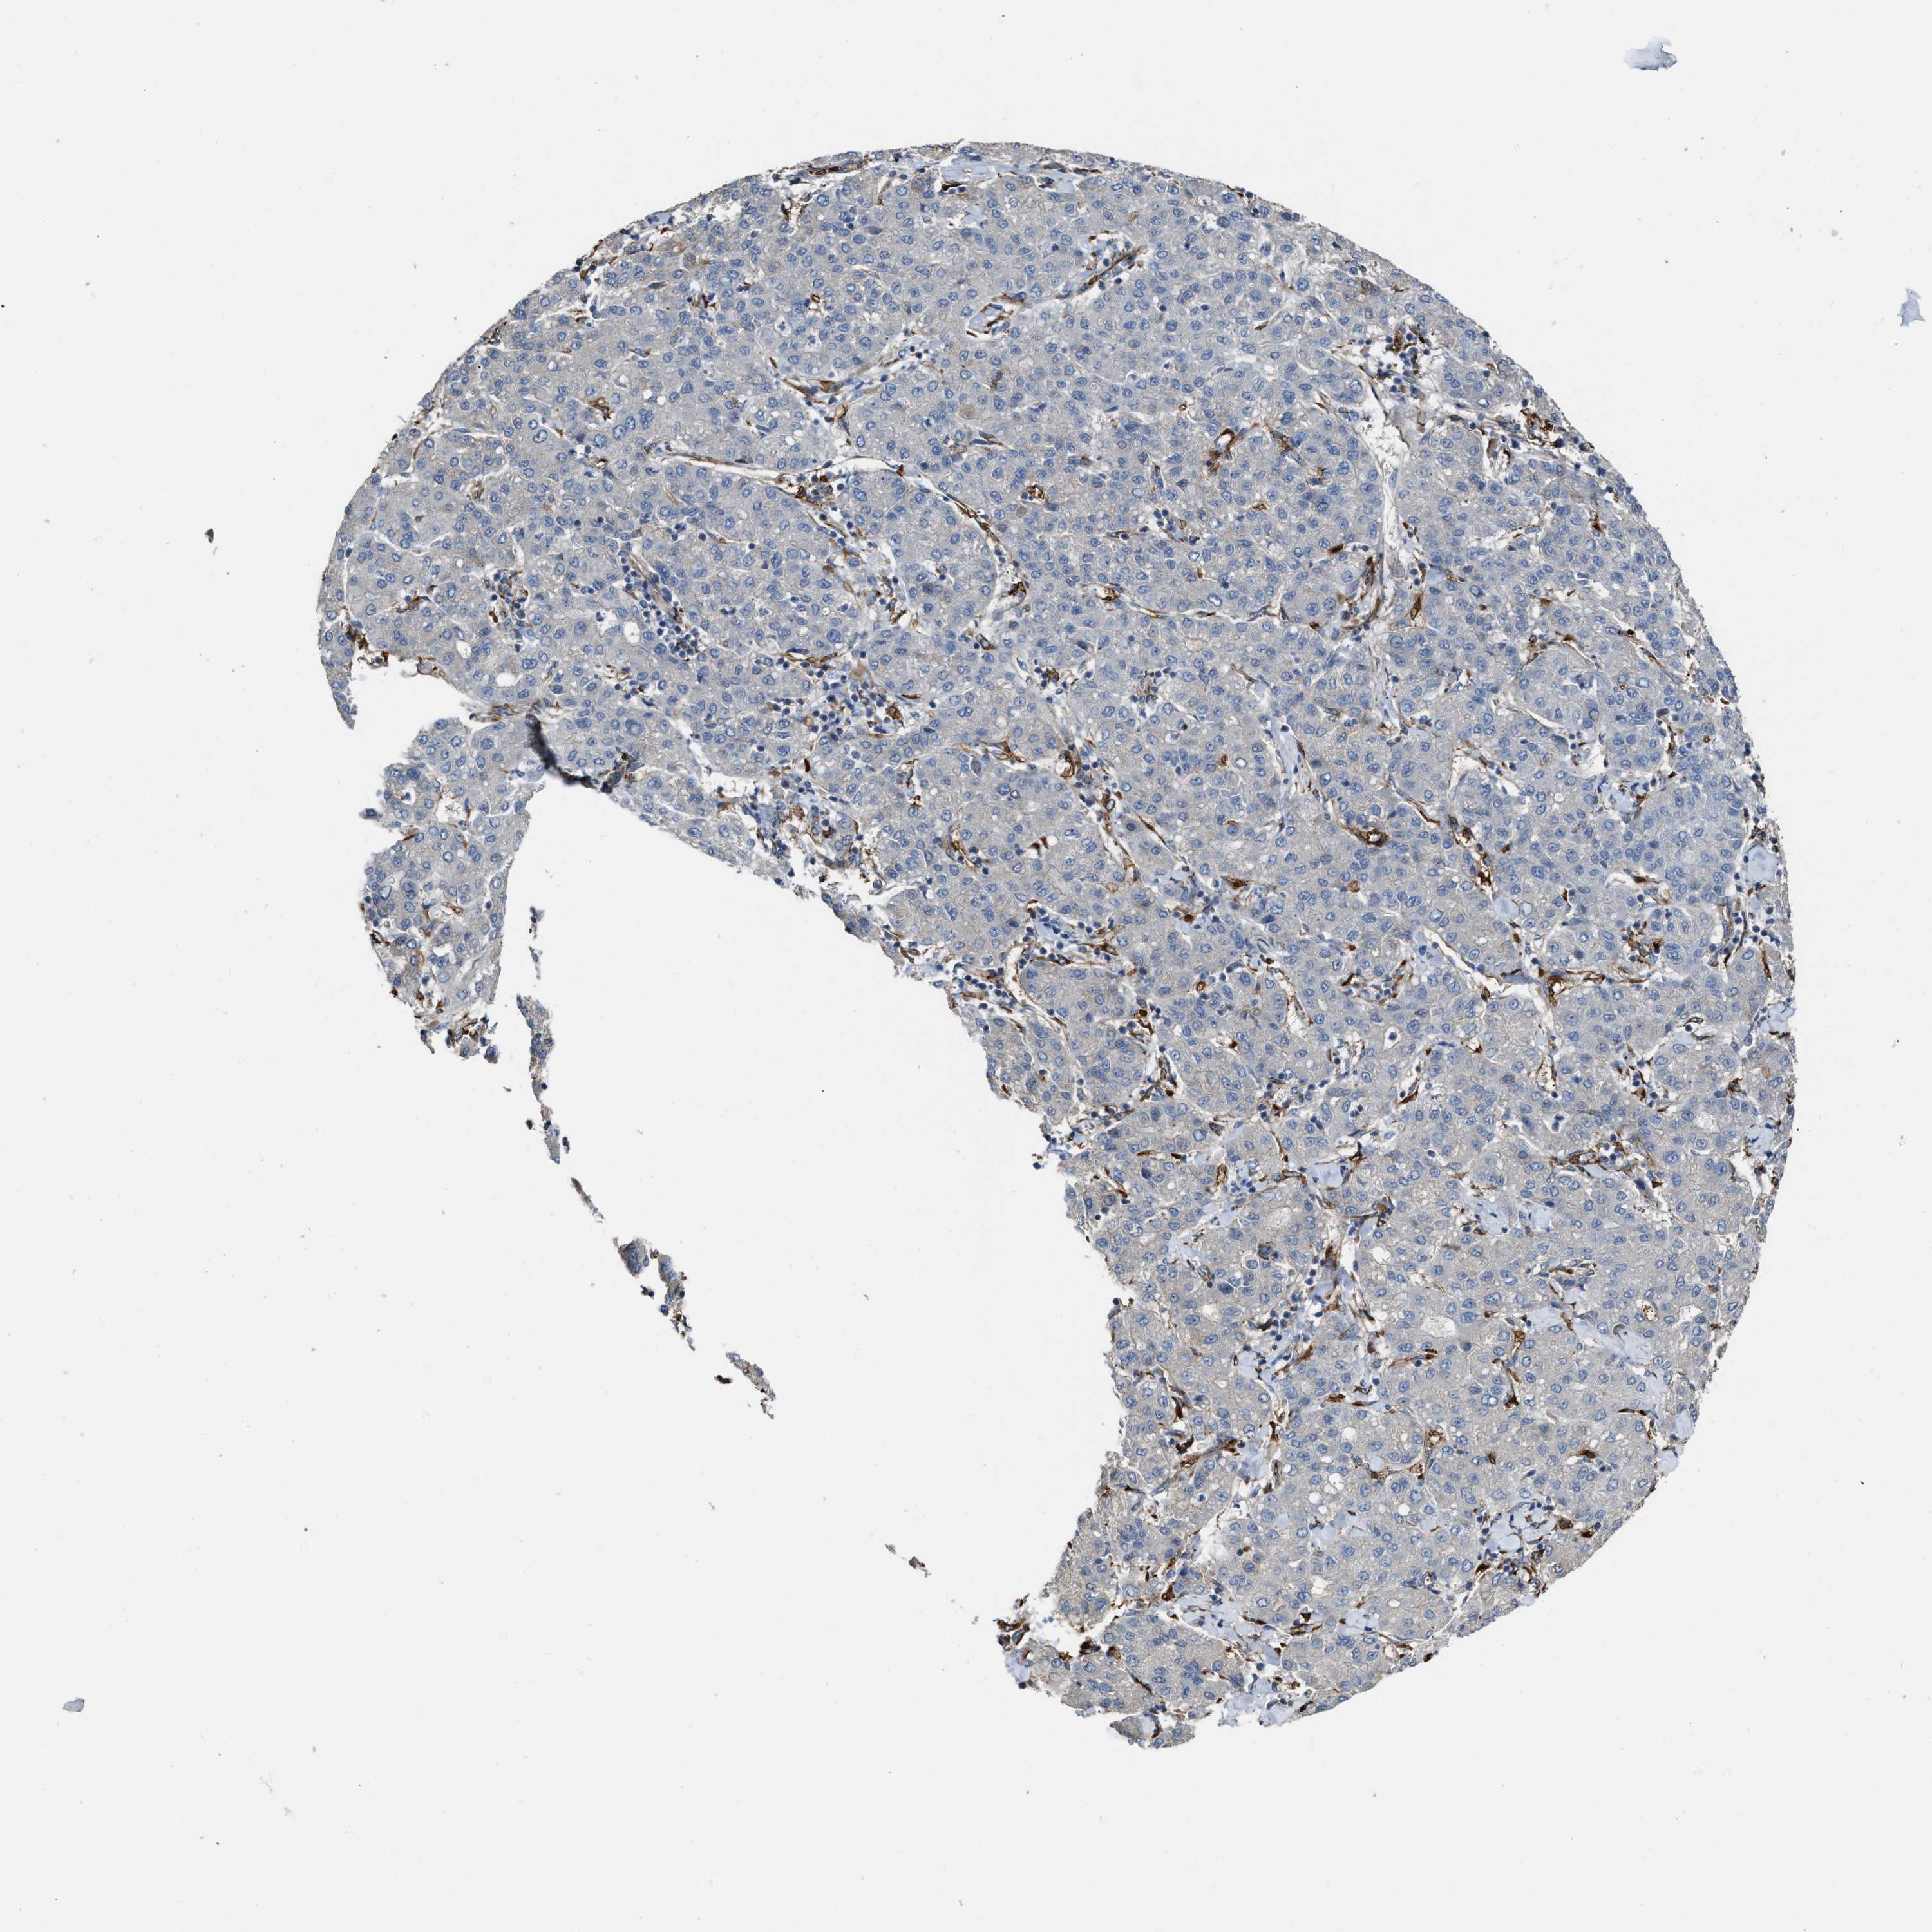

LIVER CANCER - Protein expressioni

A mouse-over function shows sample information and annotation data. Click on an image to view it in a full screen mode. Samples can be filtered based on level of antibody staining by selecting one or several of the following categories: high, medium, low and not detected. The assay and annotation is described here.

Note that samples used for immunohistochemistry by the Human Protein Atlas do not correspond to samples in the TCGA dataset.

Antibody stainingi

Antibody staining in the annotated cell types in the current human tissue is reported as not detected, low, medium, or high, based on conventional immunohistochemistry profiling in selected tissues. This score is based on the combination of the staining intensity and fraction of stained cells.

Each image is clickable and will lead to virtual microscopy that enables deeper exploration of all samples and also displays staining intensity scores, fraction scores and subcellular localization as well as patient and tissue information for each sample.

Antibody HPA019601

Antibody CAB008667

Staining

High

Medium

Low

Not detected

Intensity

Strong

Moderate

Weak

Negative

Quantity

>75%

75%-25%

<25%

None

Location

Nuclear

Cytoplasmic/membranous

Cytoplasmic/membranous,nuclear

Carcinoma, Hepatocellular, NOS

Cholangiocarcinoma